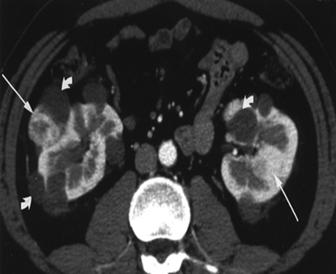

Figura 9.5. Boala von Hippel Lindau- numeroase formatini tumorele solide si chistice. (aspect macroscopic si CT) adaptat dupa Bachir Taouli, Mehdi Ghouadni, Jean-Michel Corras, Pascal Hammel, Anne Couvelard, Stphane Richard and Valrie Vilgrain: Spectrum of Abdominal Imaging Findings in von Hippel-Lindau Disease, American Journal of Roentgenology

Frecventa leziunilor renale variaza de la 30-60%. Chisturile renale simple sunt cele mai frecvente. Neoplasmele observate la 35-38% din cazuri sunt adesea bilaterale, multifocale si de talie mica.